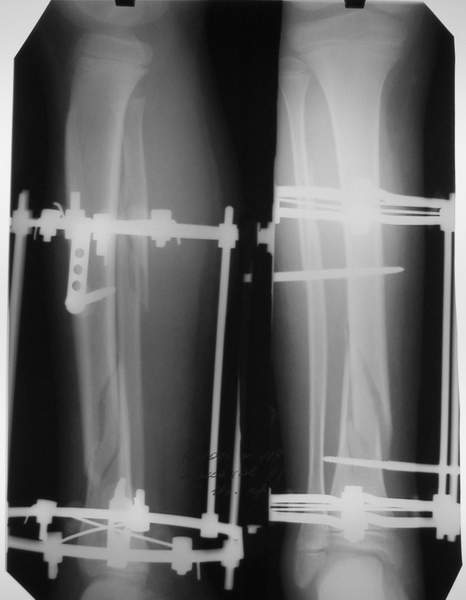

В аттачтах №№ 1 и 2 - примеры, когда 2 кольца не позволили послеоперационно

исправить смещение фрагментов большеберцовой (по ширине и вальгусное).

А казалось бы (#2) - поиграй на штангах и все влетит.

2